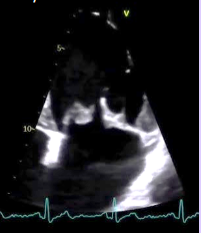

Rhabdomyoma

What is seen in this TTE?

<p>What is seen in this TTE?</p>